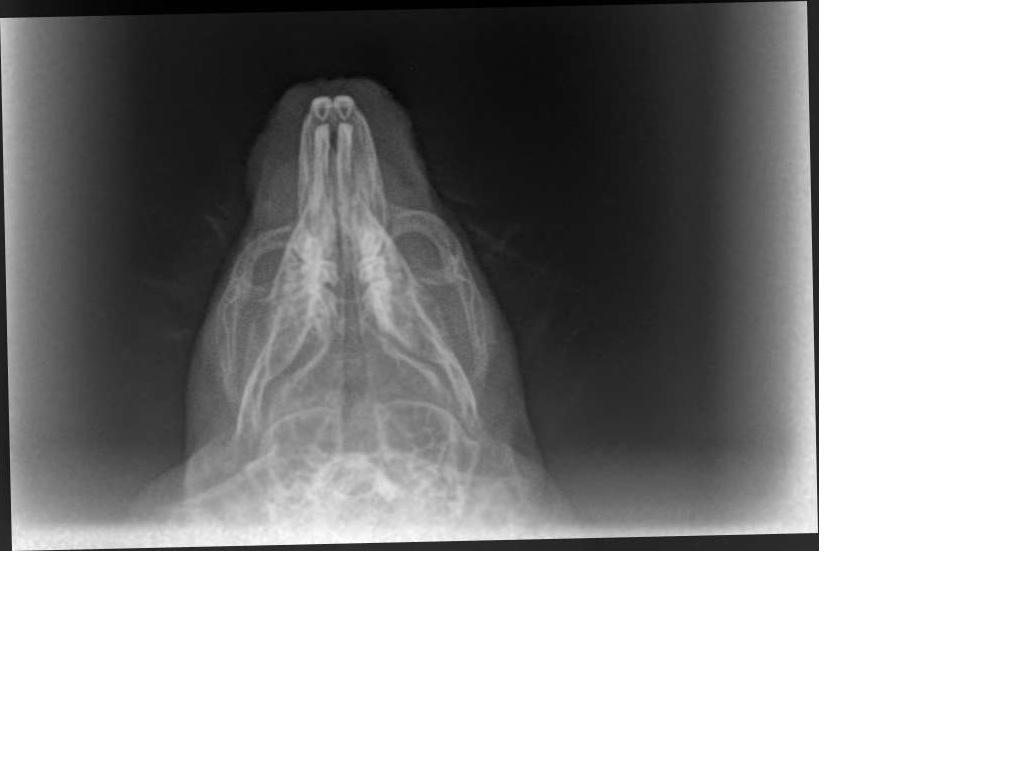

Die Röntgenbilder waren auch sehr Interessant anzusehen. Leider sieht man auf der seitlichen Aufnahme nicht sonderlich viel von dem Bruch, da sich der Knochen scheinbar nicht nach oben/unten verschoben hat.

Auf der anderen Aufnahme sah es für mich allerdings so aus, dass sich der Knochen auch ein Stück zur Seite verschoben hat. Die Bruchstelle hab ich mal eingekreist und für mich sieht es so aus, als ob die rechte und linke Hälfte des Kiefers betroffen sind.

Zum Vergleich eines von Diabolo LG

@Viktor.K laut TA war / ist es auch ein doppelter Kieferbruch, deine Einkreisung könnte also stimmen